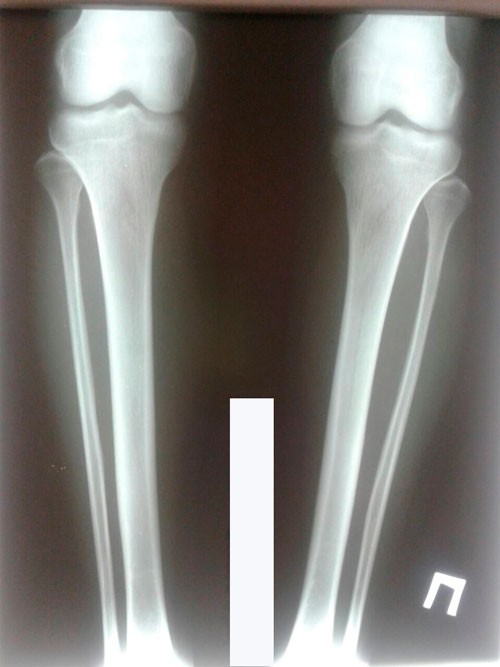

Исходник 28 лет Актобе.

Дата операции 14.02.2018г.

Дата снятия аппаратов 12.06.2018г.

Срок лечения 120 дней.